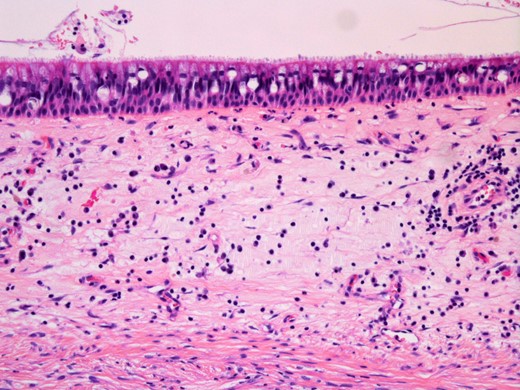

Physical examination revealed a non-tender, hard swelling of the left nasal wing from which serosanguineous fluid was aspirated by fine needle (Fig. 1). Intraoral examination showed a soft palatal expansion and on panoramic radiography, the identified cyst had no relation to the neighbouring teeth. Computed tomography showed a trilocular cyst in the left maxillary region (Fig. 2). A clinical diagnosis of surgical ciliated cyst was made, and facial osteotomy and cyst enucleation were performed under general anaesthesia. Lateral rhinotomy provided excellent exposure of the expanded cortical bone, which was removed carefully with a bone chisel. Serosanguineous fluid filled the cyst cavity just below the surface; however, palatal and nasal cyst cavities contained straw-coloured fluid. The cyst was enucleated, and the facial wound was closed primarily (Fig. 3). Healing was uneventful. Histopathological examination showed that all cyst walls were lined by ciliated columnar epithelium, which was consistent with surgical ciliated cyst (Fig. 4). The patient showed no signs of recurrence at the end of a 20-month follow-up, and the postoperative appearance was excellent (Fig. 5).

Histopathological findings of the cyst. Haematoxylin and eosin staining showing pseudostratified ciliated epithelium lining the cyst wall (original magnification ×200).